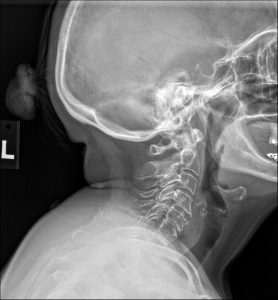

To investigate the underlying cause of her disproportionate response to a minor trauma, a standard three-view cervical spine radiographic series was ordered. The images provided a clear and immediate explanation for her clinical presentation.

On the lateral cervical view, the most striking finding is a congenital failure of segmentation involving the C6 and C7 vertebral bodies, their posterior articular pillars, and the corresponding spinous processes. This osseous fusion creates a single, solid block. At the anterior margin of this C6-C7 block, a distinct concavity or indentation is present at the level of the rudimentary disc. This feature, known as the “wasp-waist” sign, is a pathognomonic indicator of the congenital nature of the fusion.

The diagnostic story, however, does not end with the block vertebra itself. The true source of her pain and dysfunction is revealed at the adjacent motion segment above the block. The C5-C6 level demonstrates moderate to advanced degenerative changes. There is significant anterior osteophyte formation, marked narrowing of the intervertebral disc space, and notable facet arthrosis with sclerosis of the articular surfaces. These degenerative findings are far more advanced than would be typically expected for a 54-year-old, pointing to a long history of abnormal biomechanical stress. The radiology report clearly delineated these two related but distinct findings.

1. Primary Diagnosis: Congenital Block Vertebra at C6-C7. This is the underlying structural anomaly that has been present since birth.

2. Secondary Diagnosis:  Advanced Secondary Degenerative Spondylosis and Arthrosis at the Hypermobile C5-C6 Segment, presenting with an acute traumatic exacerbation. This is the acquired, pathological consequence of the primary anomaly and the direct source of the patient’s clinical symptoms.